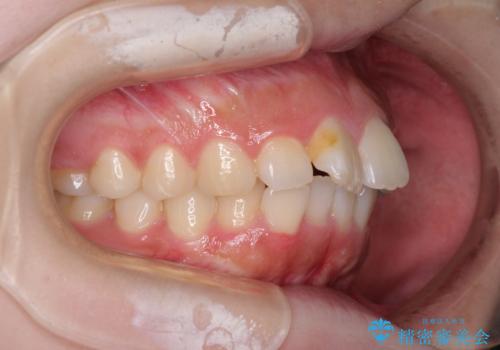

前歯のデコボコをインビザラインできれいに整える

- 前歯のデコボコと上下の隙間を気にして来院された患者様です。

前歯の捻れを改善するとともに、口元が少しでも引っ込むように治療計画を立て、仕上げることができました。